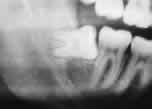

Panoramic X-Ray is a Picture of teeth, bones and soft tissues around them to help find problems which are not diagnosed with examination.

Panoramic X-Ray is a method which helps the dentist to diagnose the problems in teeth or gum. For example, X-Ray pictures can show cavities, hidden dental structures (such as wisdom teeth), and bone loss that cannot be seen during a visual examination. Also, these X-Rays do Show problems such as impacted teeth, bone anormalities, cysts, tumors, infections and fractures.